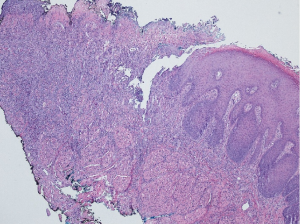

Re-analysis of previous biopsy of the lesion reveals mucosal ulceration extending deep into the underlying regional skeletal muscle tissue (Figure 2).